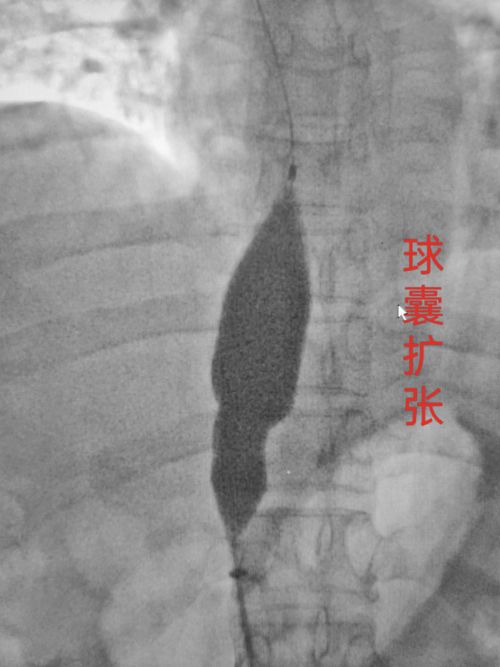

该女性50岁,因上腹部不适来我院就诊,经彩超、CT确诊为“布卡氏”综合征,肝后段下腔静脉闭塞,奇静脉,半奇静脉脉明显扩张并经上腔静脉回流入右心房。王伟迪主任会诊后决定实施下腔静脉开通术,大球囊扩张术,必要时实施支架植入术。

经医护技密切配合,手术顺利完成,达到手术预期效果。布卡氏综合征会导致肝后型门脉高压症,患者肝脏,脾脏增大水肿,腹壁静脉曲张,双下肢皮肤色素沉着。如不及时治疗会导致肝硬化,胃底食道静脉曲张破裂出血危及生命,女性患者会导致不孕不育。